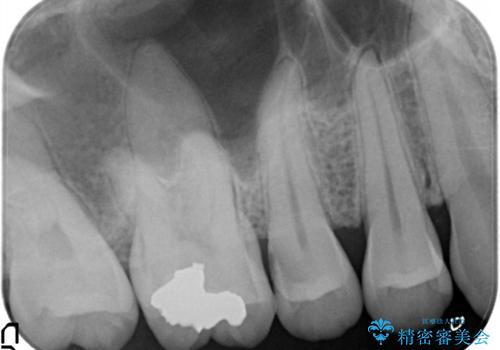

- 定期検診にて虫歯を発見したため、セラミッククラウン、セラミックインレーにて治療を行いました。

小臼歯の虫歯は歯髄に近かったため、部分的断髄法にて歯髄を部分的に保存した治療をおこなっています。

部分的断髄法を行う際は

・自発痛の既往

・冷温刺激に対する長引く疼痛

・打診

にて診断をおこない、治療が可能かどうかを判断します。